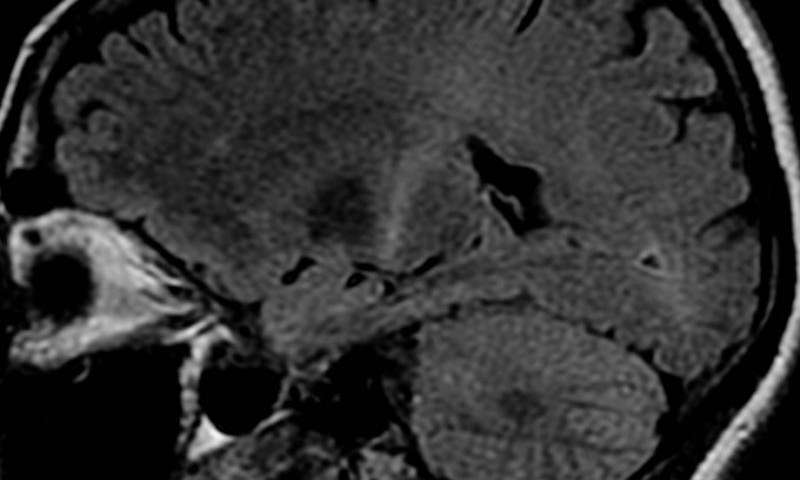

محققان به تازگی پروتئینی را کشف کرده‌اند که در ایجاد بیماری ALS نقش دارند و امیدوارند که با مورد هدف قرار دادن آن بتوانند این بیماری را درمان کنند.

به گزارش سرویس علم و فناوری جی‌پلاس، ALS به عنوان یک بیماری پیش رونده و تخریب‌کننده عصبی، توانایی حرکت و فکر کردن را از افراد مبتلا می‌گیرد. محققان دانشگاه سلامت یوتا در مطالعات اخیر به وجود نوعی پروتئین موسوم به Staufen1 دست یافته‌اند که در سلول‌های بیماران مبتلا به ALS تجمع می‌یابند.

از بین بردن این پروتئین از موش‌های بیمار، علائم بیماری را در آنها شامل عملکرد حرکتی بهبود بخشید. این نتایج حاکی از آن است که هدف قرار دادن پروتئین Staufen1 می‌تواند نتایج درمانی امیدبخشی به همراه دارد. محققان تا پیش از شناسایی ارتباط این پروتئین با بیماری ALS، هرگز تصور نمی‌کردند این پروتئین نقشی در بروز بیماری آتاکسی داشته باشد. بیماران در این بیماری کنترل حرکات خود را از دست می‌دهند.

آنها دریافتند که پروتئین Staufen1 به پروتئین Ataxin2 متصل می‌شود. پروتئین Ataxin2، پروتئینی است که مسئول بروز بیماری آتاکسی و عامل پرخطری برای ابتلا به ALS به شمار می‌رود. پزشکان با حذف ژنتیکی پروتئین Staufen1 از بدن موش‌های مبتلا به توانستند سطح فیزیولوژیکی و مولکولی موش‌ها را بهبود بخشند.

محققان درمان را در 12 هفتگی موش‌ها انجام دادند و آزمایش‌هایی که بعد از آن گرفته شد نشان داد که موش‌های درمان‌شده عملکرد جسمی خوبی از خود نشان دادند و می‌توانستند راه بروند و با سرعت بدوند. همچنین تعداد پروتئین‌هایی که در فرآیند این بیماری در سلول‌های مغزی کاهش یافته بود، دوباره به تعداد اولیه خود و حالت طبیعی برگشت. محققان، پروتئین Staufen را حدود 30 سال پیش ابتدا در مگس‌های میوه پیدا کردند اما هرگز تصور نمی‌کردند که بیماری‌زا باشند.